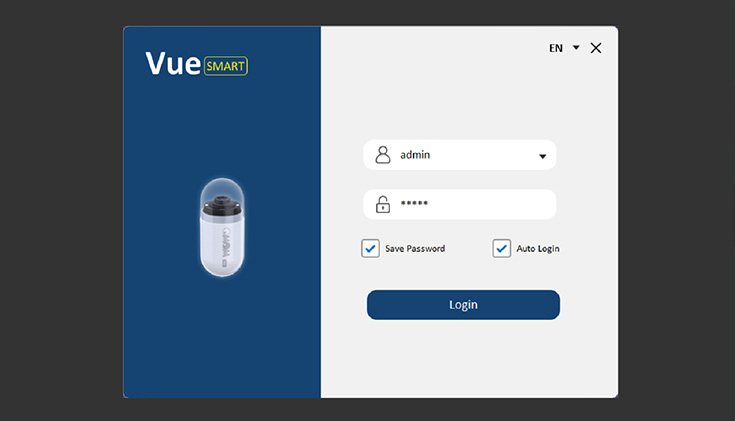

Vue Smart™

Wykorzystując zastrzeżone algorytmy sztucznej inteligencji, SmartScan przetwarza surowe pliki obrazów, usuwając do 90% nadmiarowości, identyfikując i oznaczając aż 16 rodzajów nieprawidłowości.

Tryb czytania SmartView odtwarza tylko obrazy pobrane przez Smartscan, pomagając nam szybciej poruszać się po całym filmie. Dzięki temu możemy przyspieszyć proces diagnostyczny.

Tryb czytania SmartView odtwarza tylko obrazy pobrane przez Smartscan, pomagając nam szybciej poruszać się po całym filmie. Dzięki temu możemy przyspieszyć proces diagnostyczny.